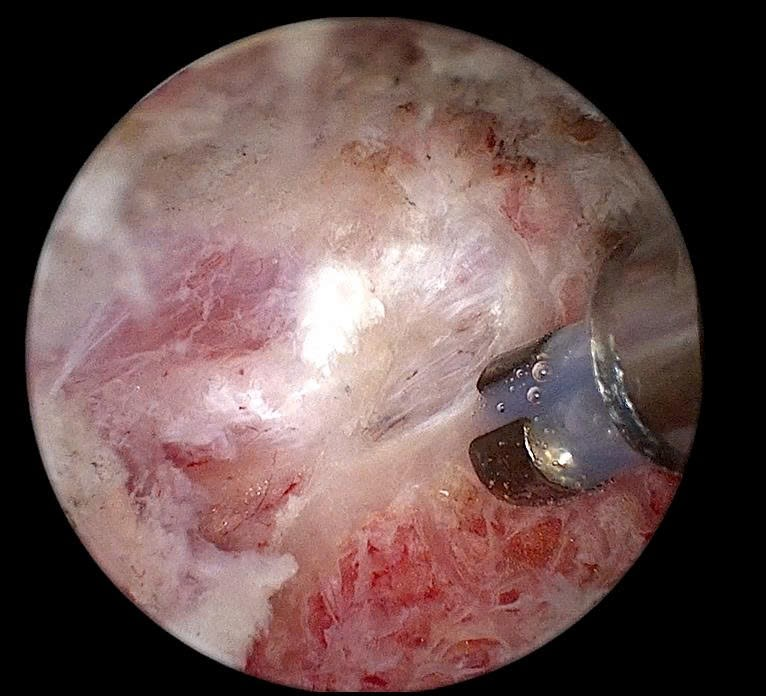

Ca phẫu thuật của bệnh nhân T. diễn ra thuận lợi và an toàn, dưới sự phối hợp của ê-kíp Gây mê hồi sức và các bác sĩ khoa Ngoại Chấn thương.

Hình ảnh tủy sống và rễ thần kinh được bộc lộ dưới camera nội soi

Theo chia sẻ của Ths. Bác sĩ Trần Bình Ngọc – Trưởng khoa Ngoại Chấn thương, Bệnh viện A – Người trực tiếp thực hiện ca phẫu thuật: “Kỹ thuật nội soi cột sống thắt lưng hai cổng điều trị thoát vị đĩa đệm hiện được xem là một trong những kỹ thuật xâm lấn tối thiểu tiên tiến trong điều trị các bệnh lý cột sống. Với hai đường rạch nhỏ khoảng 5–10mm, giúp bảo tồn tối đa cơ cạnh sống và cấu trúc cột sống. Camera độ phân giải cao hỗ trợ phẫu thuật viên quan sát rõ, bóc tách chính xác khối thoát vị và hạn chế nguy cơ tổn thương thần kinh, mang lại hiệu quả điều trị cao so với phẫu thuật mổ hở truyền thống. Ngoài ra, phương pháp này còn giúp bệnh nhân ít đau sau mổ, phục hồi nhanh, rút ngắn thời gian nằm viện”.